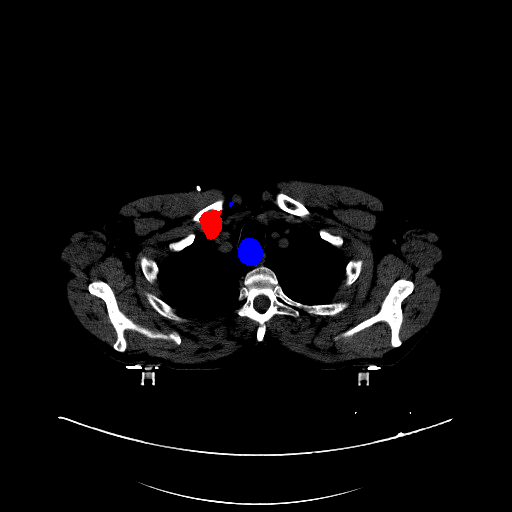

Case Study 3: Multi-Organ Segmentation

The cognition of artificial intelligence is important for computer-aided diagnostic. Multi-organ segmentation can help the machine understand the structure of the human body, which is very important for all the relevant tasks. Therefore, some research has focused on single- or multi-organ segmentation tasks, such as the liver([79, 80]) and the pancreas([81, 82]). In this case study, we use a VNet-based neural network to solve the multi-organ segmentation challenge, SegTHOR, [83]. The SegTHOR challenge includes about 40 CT images of the chest, and aims at the segmentation tasks of the heart, aorta, trachea, esophagus, and further more.

VI-1 Workflow and Implementation

As Fig. 11 shows, The workflow of this case study includes six parts: “input”, “pre-processing”, “dataset management”, “neural network”, “visualization”, and “analysis”. The “input” includes images of the chest and annotations.

“Pre-processing” rescales the range of the image values with a window width and a window level. Then, the input images are re-sampled with the “resample” tool to change their size. The “dataset management” function subsequently splits the dataset into a training and a testing set randomly, yet reproducibly.

“Neural network” employs VNet to train and validate the model, which can be used to segment organs from the chest. Then, the segmented images can be visualized via the “organ visualization” option, and the results can be analyzed with the “result analysis” tool to generate an MS-Excel based report.

VI-3 Result and Visualization